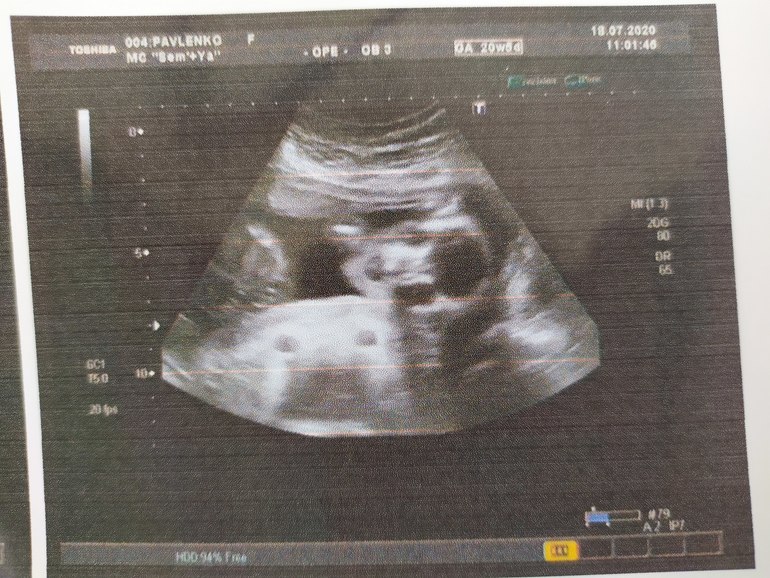

Почему-то невезëт нам с фоточками ляли. Сервис в Донецке, к сожалению, хромой на две ноги. Хотела, чтобы сделали фото "пирожочка" почëтче. Ну и профиль, что ли😁

Доктор посмотрел все очень тщательно(мне понравилось больше, чем в государственных клиниках), но сжимает наша крошка ножки(на всех УЗИ), и пол снова предположили, хотя звучало это, "скорее всего, что девочка". Сделали нам фото, когда лялька начала шевелиться и немного развела бëдрышки, но я так и не поняла - это вид спереди или сзади.

Второе фото вообще вызывает у меня разочарование, я, как Рейчел из " Друзей"( когда она первый раз сходила на УЗИ) 😆

Девочки, если есть у кого-то хоть какое-нибудь представление о втором фото - поделитесь соображениями, пожалуйста 🙏

Ничего не понятно)) было предположение, но посмотрела еще раз на фото...и нет предложений. Почему, интересно, когда они делают УЗИ, такие красивые и интересные моменты проскакивают, а как фото распечатывают- держись)))

Слушай,второе фото это кажется голова... ну там где белое-это кости...👀🙄 и овал похож именно головы...👀

Я не пойму положение, если внизу тельце, то, что это за точки? И где ручки и ножки(такое ощущение, будто они где-то сзади)

Мне кажется что там где голова и вниз просвет-это ручки-плечо и предплечье,в дальше по телу-ножки и ребёнок находится спинкой кверху) типа ползёт))))😁

Да, на первом фото видно что девочка 😍

Второе фото это малышка прямо смотрит на вас. Глазницы, носик, ротик приоткрыт. Кулачок видно рядом с личиком

На втором фото сверху сняли) видно лицо и туловище))) у меня похожее фото есть 😁